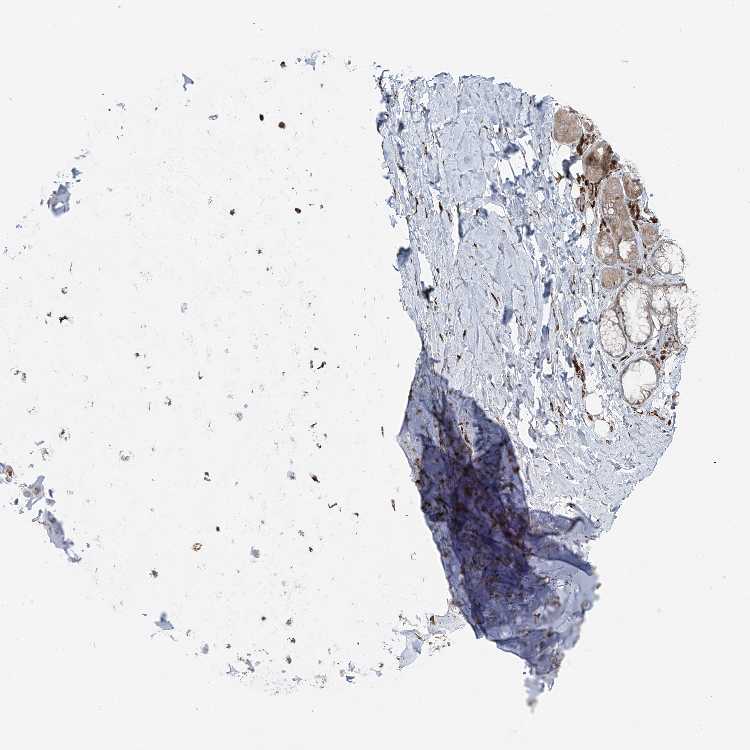

SOFT TISSUE 1 - Antibody stainingi

Antibody staining in the annotated cell types in the current human tissue is reported as not detected, low, medium, or high, based on conventional immunohistochemistry profiling in selected tissues. This score is based on the combination of the staining intensity and fraction of stained cells.

Each image is clickable and will lead to virtual microscopy that enables deeper exploration of all samples and also displays staining intensity scores, fraction scores and subcellular localization as well as patient and tissue information for each sample.

Antibody HPA031501Antibody HPA031502Antibody HPA031503

Chondrocytes Medium--

Fibroblasts MediumNot detectedLow

Peripheral nerve MediumNot detected-